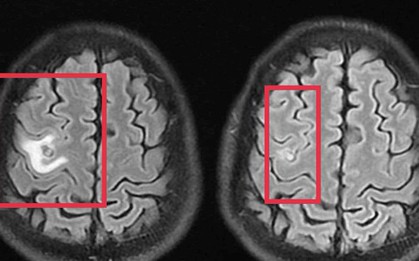

Đi khám sau 2 tuần liên tục đau đầu âm ỉ, mệt mỏi, nữ bệnh nhân ở Hà Nội phát hiện mắc áp xe não trái nên cần nhập viện điều trị.